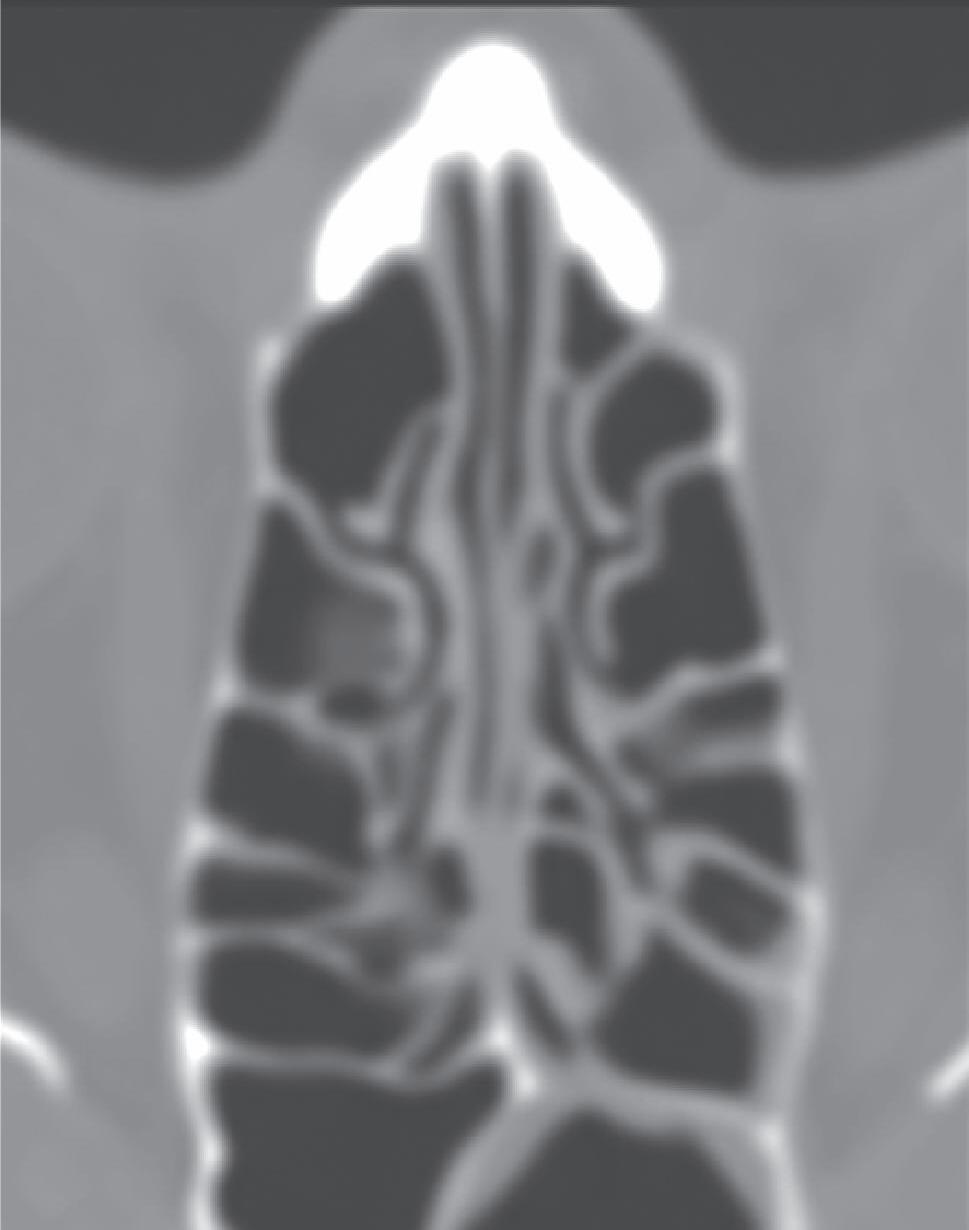

1-30. (a) Peça anatômica em corte coronal demonstrando a placa das conchas acoplada à porção inferior da lamela lateral da cribriforme e sua fixação na parede medial da órbita e na base do crânio. (b) Reconstrução tridimensional de TC com destaque para distribuição dos filetes do olfatório.